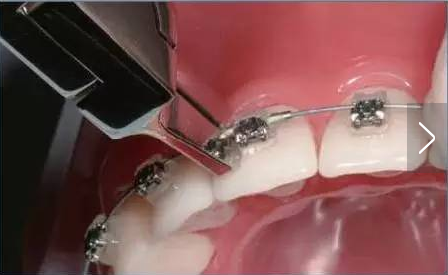

此外,由于低摩擦力的矯治環(huán)境,鎳鈦圓絲容易左右竄動(dòng)甚至從末端矯治器中滑脫出來,導(dǎo)致黏膜劃傷或潰瘍,因此弓絲的末端回彎非常必要,有時(shí)還根據(jù)需要在擁擠牙的近中(最常見于中切牙間)放置阻擋管(圖1)。

圖1 阻擋管的位置